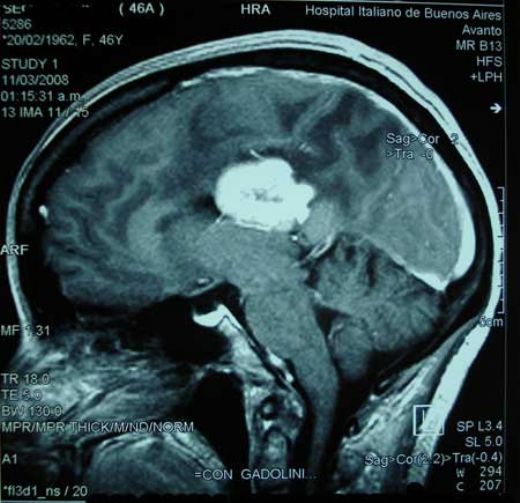

Beyinde Kitle Tanı Yöntemleri Beyinde kitle tanısı, genellikle bir dizi görüntüleme testi ve nörolojik muayene ile konulur. Bu süreçte kullanılan yaygın yöntemler şunlardır:

Efahim, baş ağrısı beyin kitlesinin yaygın belirtilerinden biridir. Bu tür bir belirti yaşamak, kitle varlığının bir habercisi olabilir, ancak her baş ağrısının bu anlama gelmediğini de unutmamak gerekir. Tedavi sürecinde, öncelikle bir nörolog veya beyin cerrahı tarafından detaylı bir inceleme ve muayene yapılması gerekir. Ardından, genellikle beyin MRı veya BT taraması gibi görüntüleme yöntemleriyle kitlenin boyutu ve konumu belirlenir. Tedavi seçenekleri arasında cerrahi müdahale, radyoterapi veya kemoterapi bulunabilir. Doktorunuz size en uygun tedavi planını belirleyecektir. Geçmiş olsun, umarım en kısa sürede sağlığınıza kavuşursunuz.